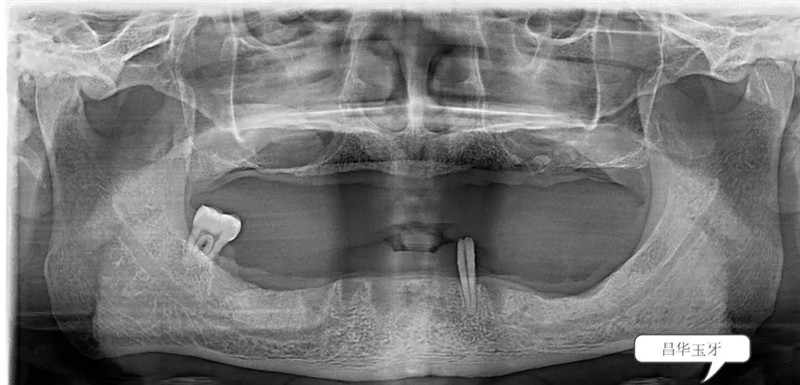

无论是直接的口腔检查还是从全景片上来看,这位患者全口牙列所剩无几,患者自述过程中亦可听出患者是饱受无牙之苦。也确实,从面容到进食再到发音均受牙齿缺失的影响。(如下图)

根据患者的口内情况,结合X光片,为患者设计全口牙种植All-on-4。并在一系列的术前准备之后,我院特邀——省口腔家白彭主任为患者植入4颗植体,手术微创、全程无痛,并在12月20日傍晚,白主任为患者装上上半口固定牙冠,患者很满意。